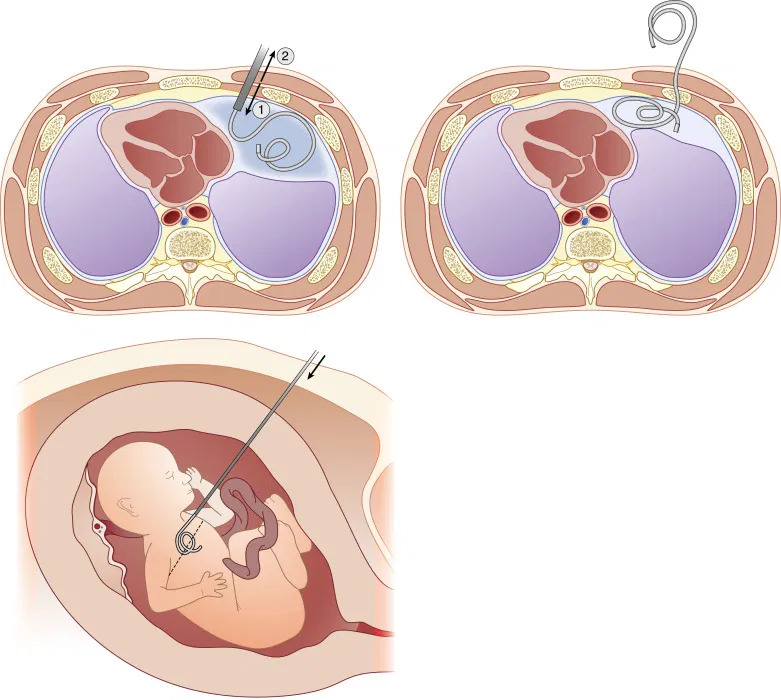

Dreno de Tórax

Também conhecidos como drenos ou shunts feto-amnióticos. São usados para drenar uma coleção de líquido de uma cavidade fetal (mais comumente o tórax, bexiga ou pelves renais) para a cavidade amniótica através da inserção de um cateter específico guiado por ultrassonografia. Como trata-se de um procedimento invasivo, é realizado em ambiente hospitalar.

As indicações das derivações fetais são as seguintes:

⦁ Derrames pleurais associados a hidropisia (Figura 1);

⦁ Malformações adenomatóide cística do pulmão tipo I associado a hidropisia que não responderam a tratamento medicamentoso prévio;

⦁ Obstrução urinária baixa ou obstrução urinária alta bilateral cursando com anidrâmnio (ausência de líquido amniótico).

Cada caso deve ser avaliado individualmente e avaliado a necessidade de colocação do dreno.

Figura 1: Inserção do dreno no tórax do feto que apresenta derrame pleural – Shunt tóracoamniótico.